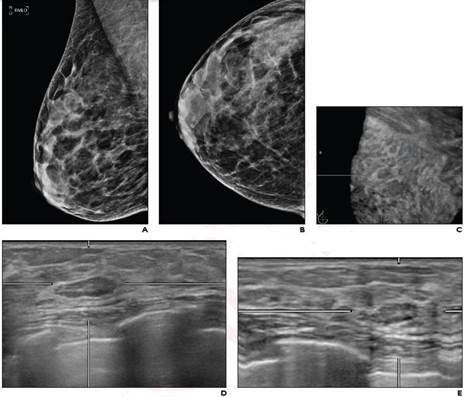

The Addition Of Automated Breast Ultrasound To Mammography In Breast Cancer Screening Decreases Stage At Diagnosis Academic Radiology

The Addition Of Automated Breast Ultrasound To Mammography In Breast Cancer Screening Decreases Stage At Diagnosis Academic Radiology from els-jbs-prod-cdn.jbs.elsevierhealth.com

(1) gary ulaner, md, phd, facnm. Other ultrasound findings that suggest breast cancer include: If your breast tissue is too dense for a mammogram. Mri has a wide spectrum of findings for fat. Among all cancers in women, he takes the initial place. If you're younger than 25. Breast ultrasound images are seen from superficial (skin) to deep (chest wall muscle) over a segment of tissue. This image is a mammogram of a normal fatty breast, typical of older women, that does not have a lot of dense tissue.

Both the mammogram and ultrasound looked fuzzy and gray on the screen and i have no idea. It is the most common cause of cancer death in women. in 2005 alone, 519 000 deaths were recorded due to breast cancer. this means that one in every 100 deaths worldwide and almost one in every 15 cancer deaths were due to breast cancer. Mri has a wide spectrum of findings for fat. A specialist looks at the ultrasound pictures. This high amount of echo results in a bright white spot appearing on the ultrasound image. You may notice dimpling or pitting, and the skin on your breast. On ultrasound, a breast cancer tumor is often seen as hypoechoic, has irregular borders, and may appear spiculated. What does cancer look like on a breast ultrasound breast cancer. What does a solid mass look like in an ultrasound breast image? In most cases, breast cancers develops inside the presence of precancerous changes. The outer edges of these cells look fuzzy or spiky (called spiculated). If you're younger than 25. If a solid lump shows on the scan you might need to have.

The breast tissue kind of looks like waves on the ocean. This type of cancer also changes the appearance of your breasts. What does a solid mass look like in an ultrasound breast image? This is because it may miss some early signs of cancer. Breast ultrasound images are seen from superficial (skin) to deep (chest wall muscle) over a segment of tissue. On ultrasound, a breast cancer tumor is often seen as hypoechoic, has irregular borders, and may appear spiculated. It is the most common cause of cancer death in women. in 2005 alone, 519 000 deaths were recorded due to breast cancer. this means that one in every 100 deaths worldwide and almost one in every 15 cancer deaths were due to breast cancer. On ultrasound, a breast cancer tumor is often seen as hypoechoic, has irregular borders, and may appear spiculated.